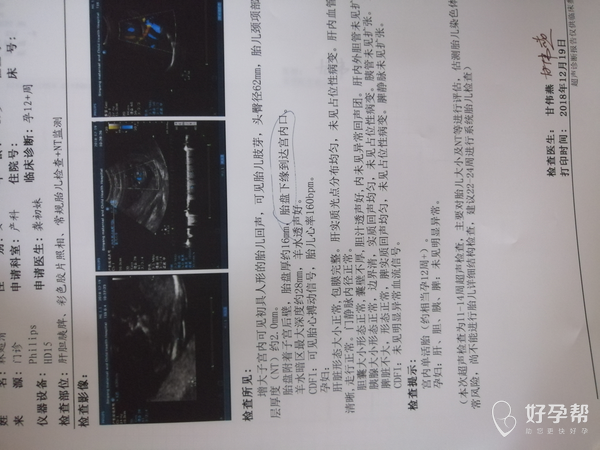

你好,孕12周,可以nt排畸检查,同时观察到胎盘下缘距离宫颈口比较近,为胎盘低置,随着妊娠月份增加,会逐渐往上生长的,需要定期复查。胎盘低置状态比较常见,不要剧烈活动及久坐久站,尽量卧床休息,禁止性生活刺激,增加休息时间,一般没有腹痛出血的情况,暂时观察就可以。怀孕28周胎盘下缘覆盖宫颈内口才能诊断前置胎盘,根据你提供的信息,你现在怀孕12周,随着孕周增大,胎盘自己会慢慢长上去一点,但是完全长上去不可能,有可能是边缘性前置胎盘,今后加强产检,饮食以清淡为主,多吃高维生素高蛋白的食物,不能吃辛辣刺激性的食物,有利于胎儿的生长发育,多吃蔬菜水果,保持大便通畅,用高点的坐便器,放松心情,你的心情对胎儿的生长发育有很大的影响的,没事的,放心吧,祝好孕!觉着我的回复对您有帮助,记着帮忙点击采纳,谢谢!